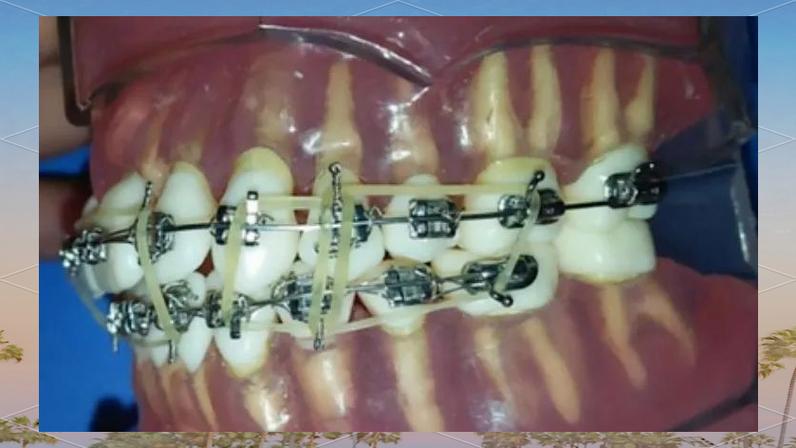

颌间牵引是通过连接上下颌牙齿的牵引装置,纠正上下颌牙弓及颌骨间的位置关系,常用于Ⅱ类、Ⅲ类错畸形的矫正,其图片特征表现为:

- 咬合关系动态:口内正面或咬合面图片中,可见上下颌牙齿通过橡皮圈(如“Ⅲ类牵引”“Ⅱ类牵引”)连接,类牵引时,橡皮圈一端挂在上颌第一磨牙颊面管,另一端挂于下颌尖牙托槽,图片可清晰显示下颌尖牙向近中、上颌磨牙向远中的移动趋势;

- 中线对齐情况:正面张口位图片可观察上下颌中线是否对齐,对于偏颌畸形患者,牵引过程中图片显示中线逐渐居中,面部不对称得到纠正。